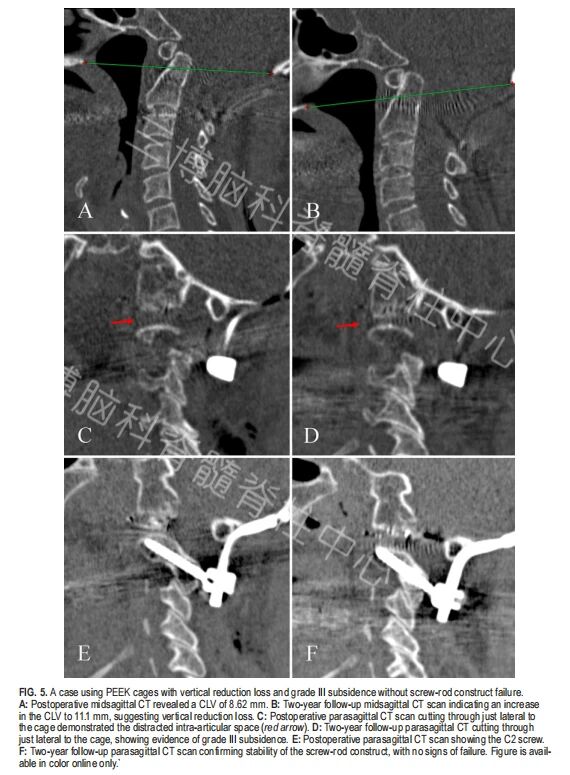

▲图5:一例患者随访过程中出现III度融合器沉降、垂直复位丢失